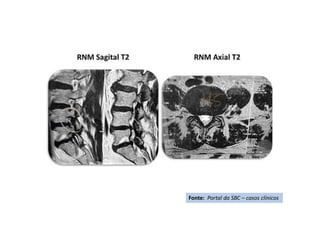

Disc protrusion-T2 weighted magnetic resonance images

of the lumbar region of the vertebral column. A. Sagittal plane. B. Axial plane.